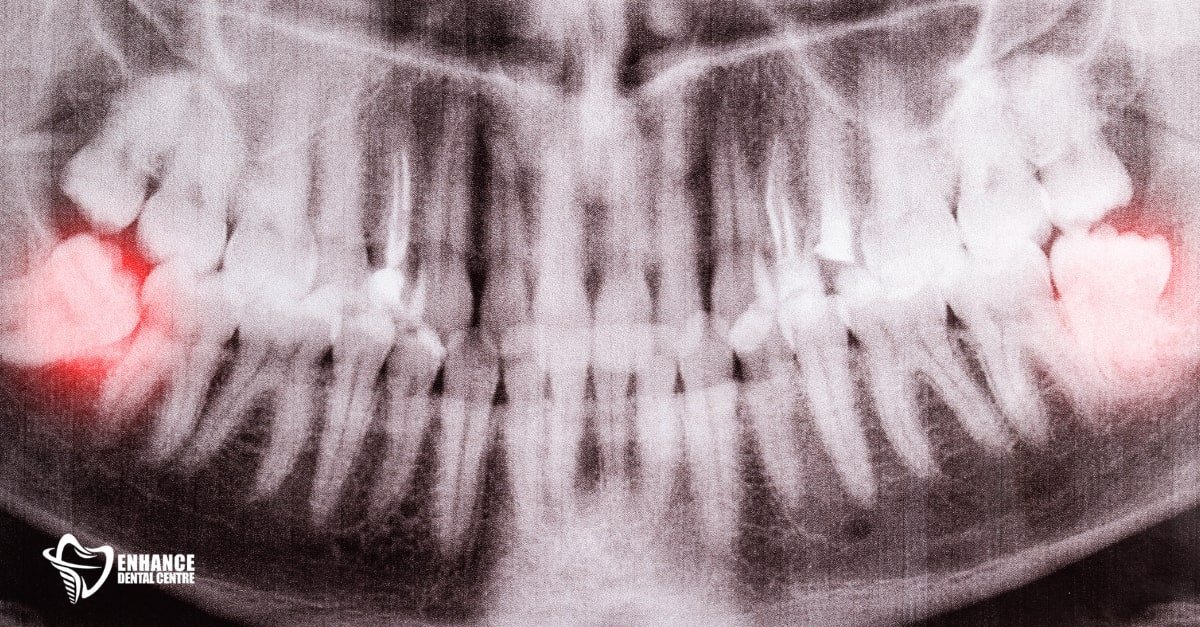

Impacted vs. Erupted Teeth

When wisdom teeth have fully erupted and are easy to access, the extraction is usually straightforward, resulting in a quicker recovery.

However, impacted teeth—those trapped beneath the gums or growing at odd angles—require more invasive surgery, often involving gum incisions or bone removal. This typically leads to increased swelling and a longer healing period.